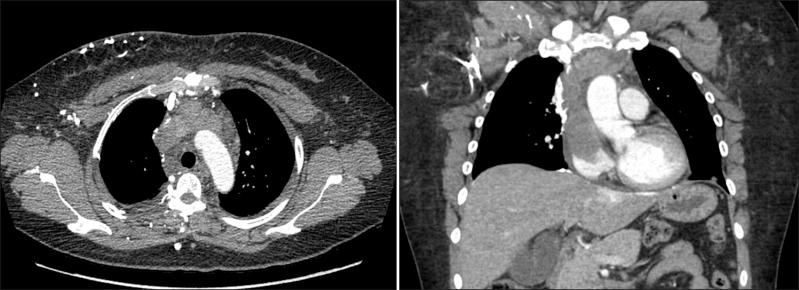

Superior vena cava syndrome (SVCS) is usually caused by extrinsic compression or invasion of the superior vena cava (SVC) by malignant tumors involving mediastinal structures. Although thymomas are well-known causes of SVCS, cases of SVCS caused by malignant thymomas protruding into adjacent vessels draining the SVC with thrombosis have been very rarely reported worldwide. We experienced a 39-year-old female patient with SVCS that developed after the direct invasion of the left brachiocephalic vein (LBCV) and SVC by an anterior mediastinal mass with a high maximum standardized uptake value on the chest computed tomography (CT) and positron emission tomography-CT. Based on these results, she underwent en bloc resection of the tumor, including removal of the involved vessels, and was eventually diagnosed as having a type B2 thymoma permeating into the LBCV and SVC. We present this case as a very rare form of SVCS caused by an invasive thymoma.

上腔静脉综合征(SVCS)通常是由涉及纵隔结构的恶性肿瘤对外侧上腔静脉(SVC)的外在压迫或侵犯所致。虽然胸腺瘤是SVCS的常见病因,但全球范围内,由恶性胸腺瘤突入引流SVC的相邻血管并伴有血栓形成导致SVCS的病例却鲜有报道。我们接诊了一名39岁的女性SVCS患者,该患者因前纵隔肿物直接侵犯左头臂静脉(LBCV)和SVC而发病,胸部计算机断层扫描(CT)及正电子发射断层扫描-CT显示该肿物的最大标准摄取值较高。基于这些检查结果,患者接受了肿瘤整块切除术,包括切除受累血管,最终被诊断为B2型胸腺瘤侵犯LBCV和SVC。我们将此病例作为侵袭性胸腺瘤导致的一种极为罕见的SVCS形式进行展示。